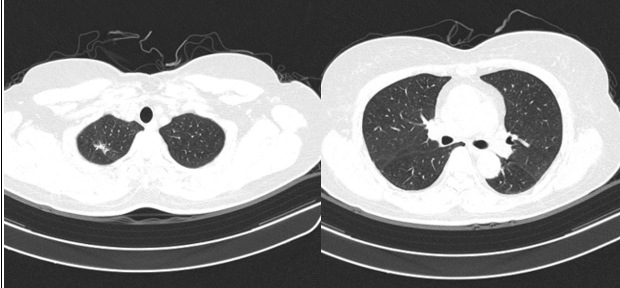

– Chụp cắt lớp vi tính lồng ngực: Nhu mô thùy trên phổi (Phải) có nốt tổn thương kích thước 13x14mm, bờ không đều, ngấm thuốc, sau tiêm. Rải rác nốt đặc 2 bên thùy phổi kích thước 3-10mm. Trung thất các nhóm 1R; 2R; 4R; 5; 8; 10RL có vài hạch lớn nhất kích thước 26x15mm; bờ không đều; ngấm thuốc không đồng nhất sau tiêm. Thượng đòn 2 bên có vài hạch tính chất tương tự; hạch bên phải kích thước 11x14mm

Hình 1. Hình ảnh cắt lớp vi tính ngực có tiêm: thùy trên phổi (P) có nốt tổn thương kích thước 13x14mm, bờ không đều, ngấm thuốc, sau tiêm. Nghi ngờ tổn thương nguyên phát (mũi tên đỏ)

Hình 2: Hình ảnh cắt lớp vi tính ngực có tiêm: Rải rác nốt đặc 2 bên thùy phổi kích thước 3-10mm (các mũi tên màu xanh lá)

Hình 3: Hình ảnh cắt lớp vi tính ngực có tiêm: Trung thất các nhóm 1R; 2R; 4R; 5; 8; 10RL có vài hạch lớn nhất kích thước 26x15mm; bờ không đều; ngấm thuốc không đồng nhất sau tiêm (mũi tên màu cam)

– Cắt lớp vi tính lồng ngực: đám xẹp đông đặc đỉnh phổi phải kích thước 11mm; nhu mô phổi rải rác nốt đặc 5-10mm. Trung thất cân đối có vài hạch 10mm

Hình 6: Hình ảnh cắt lớp vi tính ngực có tiêm: đám xẹp đông đặc đỉnh phổi phải kích thước 11mm (mũi tên xanh nước biển)

Hình 7: Hình ảnh cắt lớp vi tính ngực có tiêm: Trung thất cân đối có vài hạch 10mm (mũi tên vàng). Hạch trung thất giảm kích thước rất nhiều chỉ sau 03 chu kỳ.

– Cắt lớp vi tính lồng ngực: Đám xẹp vùng đỉnh phổi phải, nốt đặc nhỏ kích thước 2-3mm. Không thấy hạch to hay khối trong trung thất

Hình 10: Hình ảnh cắt lớp vi tính ngực có tiêm: Đám xẹp vùng đỉnh phổi phải, nốt đặc nhỏ kích thước 2-3mm

Hình 11: Hình ảnh cắt lớp vi tính ngực có tiêm: Không thấy hạch to hay khối trong trung thất

Nhận xét: Chỉ sau 03 chu kỳ Pemetrexed – Carboplatin – Pembrolizumab, hình ảnh chụp cắt lớp vi tính cho thấy tổn thương phổi nguyên phát và các hạch giảm kích thước đáng kể. Đáp ứng điều trị được đánh giá là đáp ứng một phần theo tiêu chuẩn RECIST 1.1. Sau 9 chu Pemetrexed – Pembrolizumab, bệnh nhân tiếp tục ghi nhận cải thiện rõ rệt các triệu chứng lâm sàng, thể trạng ổn định, không xuất hiện tác dụng không mong muốn nghiêm trọng. Đánh giá trên hình ảnh chụp cắt lớp vi tính cho thấy tổn thương phổi nguyên phát tiếp tục giảm kích thước không ngấm thuốc chỉ còn là đám xơ xẹp vùng đỉnh phổi phải, các hạch trung thất và ngoại vi thu nhỏ rõ rệt, không phát hiện được trên phim chụp và không ghi nhận tổn thương di căn mới.